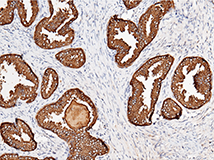

Anti-KLK3/PSA Antibody, Mouse mAb

Applications: IHC-P

(Cat#: 10771-MM02)

Immunochemical staining of human KLK3 in human prostate. Image Credit: Sino Biological US Inc.